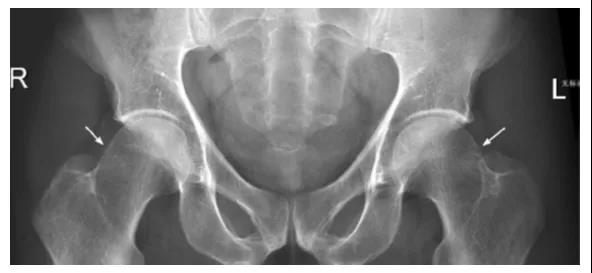

FAI影像学检查前后位片:可见股骨头不同程度的手枪柄样畸形侧位片: 观股骨头颈交界处骨性隆起;CE角﹥40°;髋臼后倾畸形;股骨颈的囊性变

FAI:齿轮型(cam-type )影像:股骨头、颈间的凹陷不足,可伴局部的骨质增生、硬化、囊变部位:前外股骨头、颈交界区